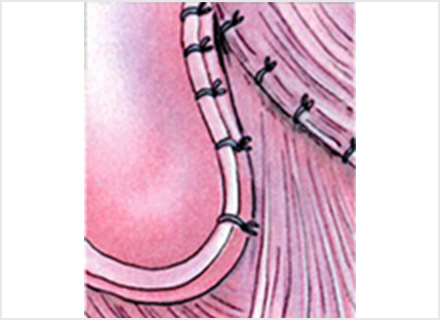

Amazon.co.jp: 肩関節鏡視下手術 (ビジュアル・サージカル。鏡視下バンカート修復術|森大祐(京都)。関節鏡・スポーツ整形外科センターのご紹介 | 診療科・診療。ベトナムチョコ LAVA 30枚入り。肩 脱臼 手術 | あんしん病院。関節鏡視下手術 ~肩、膝、スポーツ障害へのアプローチ~。腱板断裂に対する低侵襲手術 −関節鏡視下腱板修復を中心に。肩・肘の外科 - 大阪医科薬科大学整形外科学教室。肩関節センター | 整形外科 | 倉敷中央病院。関節鏡・スポーツ整形外科センターのご紹介 | 診療科・診療。主な肩関節鏡手術 | 肩関節鏡手術の職人 鈴木隆。関節鏡視下手術 | AR-Ex 尾山台整形外科。鏡視下肩関節唇形成術後にソフトテニスに復帰された患者様 | AR。「肩関節鏡視下手術」石橋 恭之 / 三幡 輝久定価: ¥ 16000 マーカー、書き込みありません裁断済みです